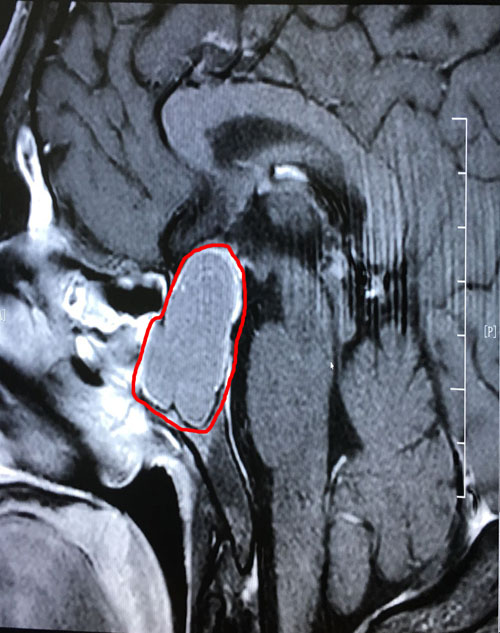

術(shù)前影像顯示:垂體巨大腺瘤,突破鞍隔向上生長(zhǎng)

到院后,李士其教授和潘仁龍主任一起,研究討論了患者病情:由于患者顱內(nèi)鞍區(qū)的腫瘤很大(約1.8*3.1公分),已嚴(yán)重影響到患者的垂體功能,并壓迫視神經(jīng),感覺(jué)神經(jīng)等功能。李士其教授表示:手術(shù)是刻不容緩的事,待患者檢查結(jié)果出來(lái),沒(méi)有手術(shù)禁忌,就可以立即實(shí)施手術(shù)。